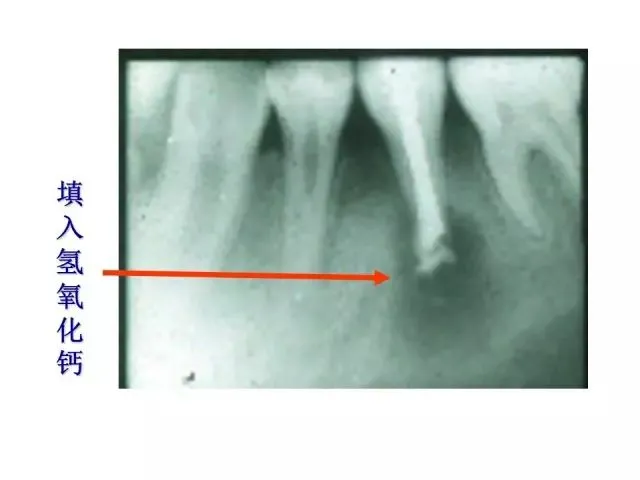

>PPT典藏 | 根尖诱导成型术

PPT典藏 | 根尖诱导成型术